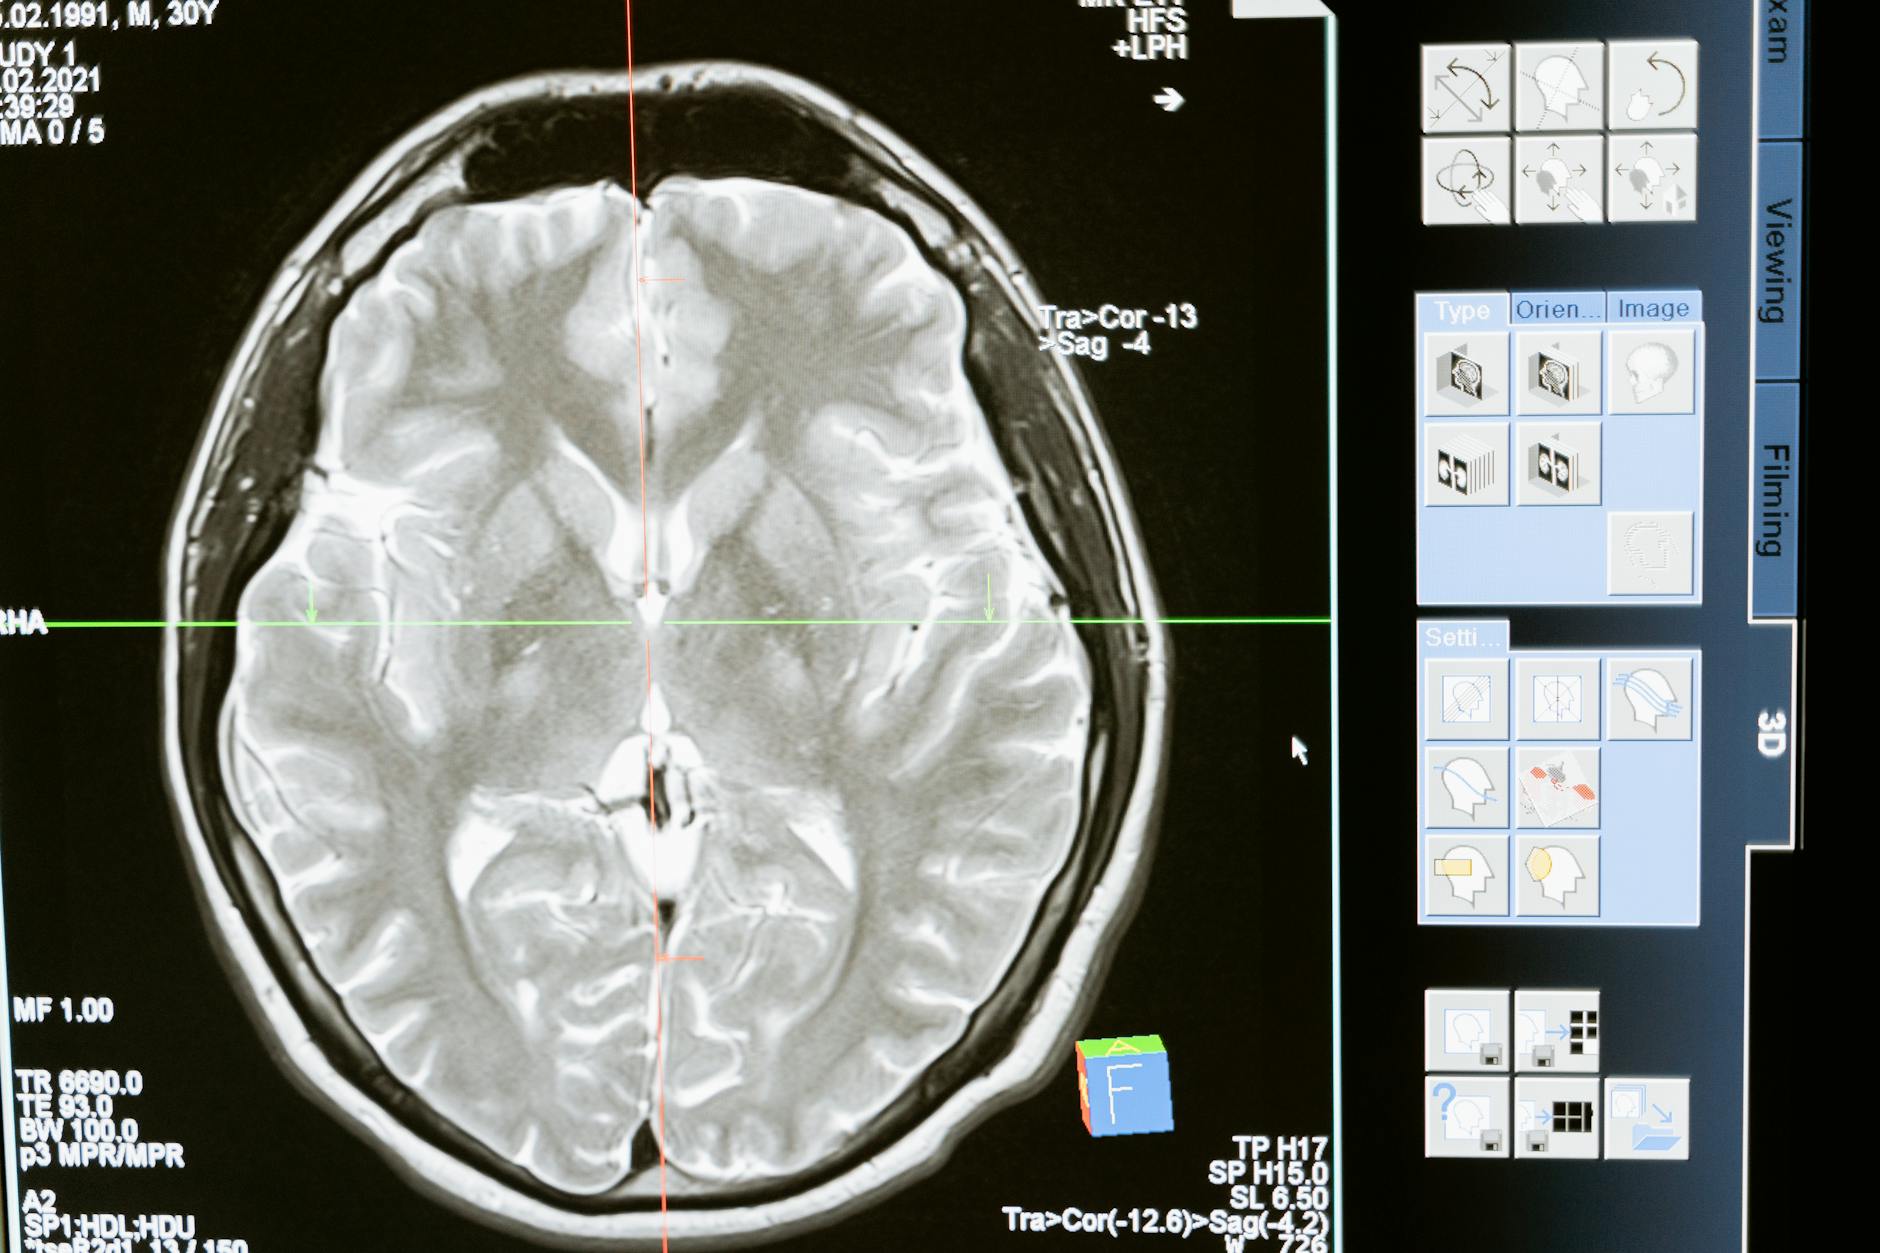

technology computer head health